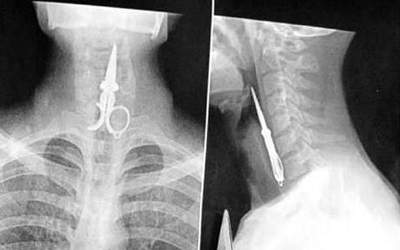

(這是用吞的??????????)